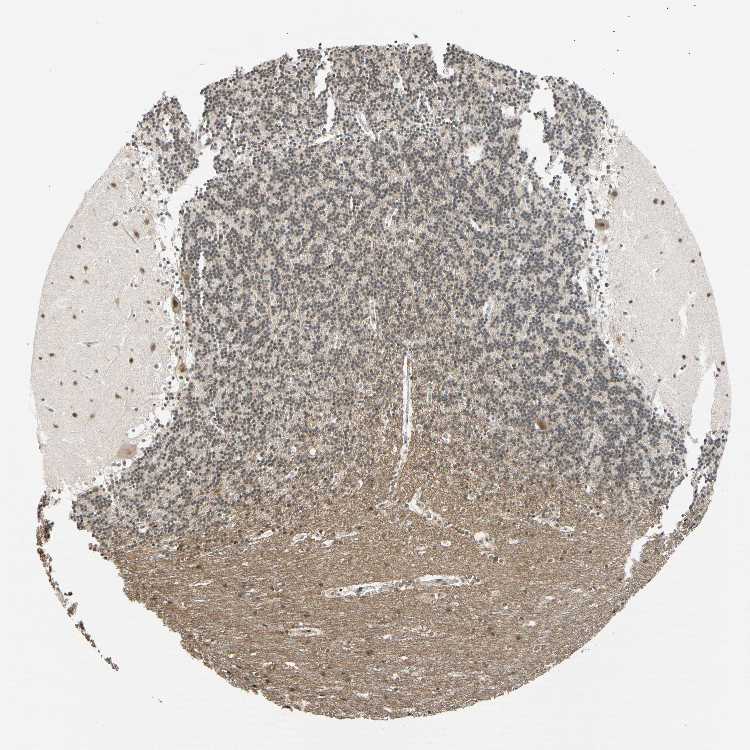

BRAIN CEREBELLUM Show tissue menu

CEREBELLUM - Expression summary

CEREBELLUM - Antibody stainingi

Antibody staining in the annotated cell types in the current human tissue is reported as not detected, low, medium, or high, based on conventional immunohistochemistry profiling in selected tissues. This score is based on the combination of the staining intensity and fraction of stained cells.

Each image is clickable and will lead to virtual microscopy that enables deeper exploration of all samples and also displays staining intensity scores, fraction scores and subcellular localization as well as patient and tissue information for each sample.

Antibody HPA008599Antibody CAB031484

Purkinje cells LowMedium

Cells in granular layer LowMedium

Cells in molecular layer MediumMedium